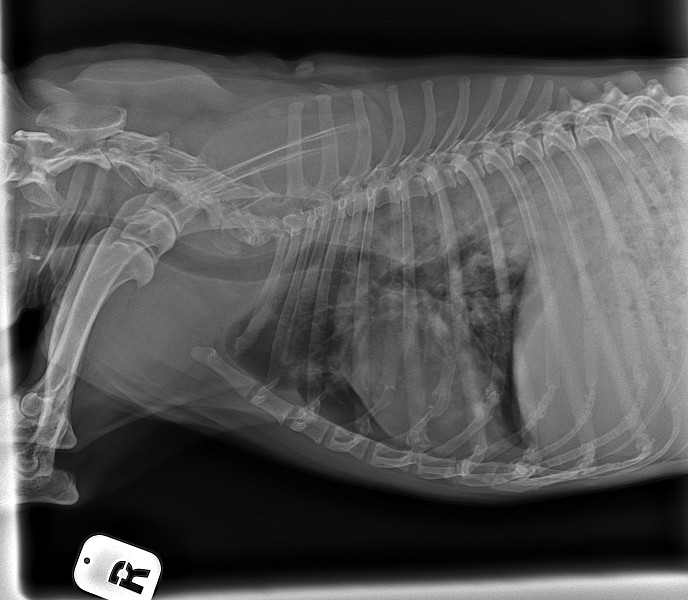

Добрый день!собачка кобель цвергпинчер 14 лет 10 месяцев,стал часто дышать,сделали рентген,помогите понять что с ним!

Ренген

Добрый день!ренген лёгких у собаки помогите прояснить ситуацию!сделали в связи с частым дыханием

Здравствуйте, у собаки выраженное затемнение по каудальным долям легких. Более всего это похоже на пневмонию.